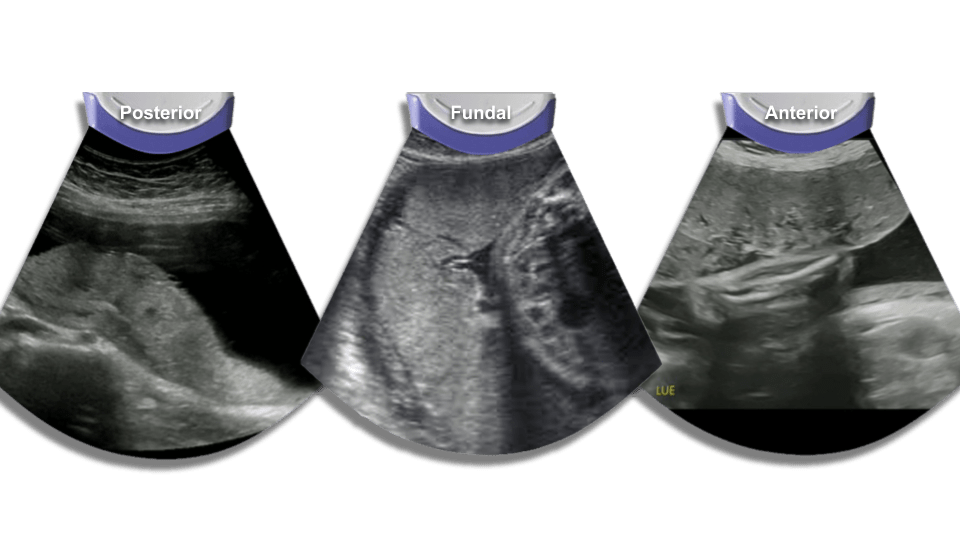

Placenta

Check for position (fundal, posterior, anterior, previa). Check the cord insertion into the placenta as well.

Placenta previa

Placenta previa is a condition in which the placental tissue lies abnormally close to the internal cervical os. The 4 generally recognized subtypes are

- Complete – the placenta is covering the entirety of the internal os

- Partial – the placenta is covering a portion of the internal os

- Marginal, in which the placental tissue abuts but does not cover the internal cervical os; and